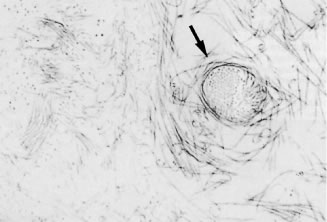

Ultrastructural studies103 have demonstrated that collagen fibrils are the only microscopic structures that could correspond to these fibers. These studies also detected the presence of bundles of packed, parallel collagen fibrils (Fig. 5). It has been hypothesized that visible vitreous fibers form when HA molecules no longer separate microscopic collagen fibrils, resulting in the aggregation of collagen fibrils into bundles from which HA molecules are excluded. Eventually the aggregates of collagen fibrils attain sufficiently large proportions and can be visualized in vitro (see Figs. 3 and 4) and clinically. The areas adjacent to these large fibers have a low density of collagen fibrils separated by HA molecules and, therefore, do not scatter light as intensely as the larger bundles of aggregated collagen fibrils. These adjacent channels probably offer relatively less resistance to bulk flow through the vitreous body and are the areas visualized in studies88,104 using India ink to fill the channels. There are changes occurring in these fibrous structures throughout life,50,100 which probably result from age-related biochemical alterations in the composition and organization of the molecular components that simultaneously result in vitreous liquefaction and fiber formation.

Fig. 5. Ultrastructure of human vitreous. Although specimens were centrifuged to concentrate structural elements, there were no membranes or membranous elements. Only collagen fibrils were detected. There were also bundles of parallel collagen fibrils such as the one shown here in cross section (arrow). (From Sebag J, Balazs EA: Morphology and ultrastructure of human vitreous fibers. Invest Ophthalmol Vis Sci 30:187, 1989.)